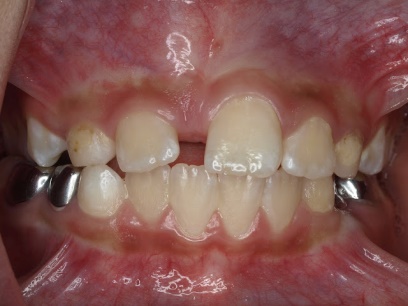

Răng thừa (a) làm R11 (b) bị kẹt không mọc ra được Tạo khoảng trước phẫu thuật

Phẫu thuật lấy răng thừa sau 4 tháng tạo khoảng Chỉnh nha kéo R11 ngầm lên

Qúa trình chỉnh nha kéo răng cửa mọc ngầm hoàn tất

Hình 5: Minh họa phẫu thuật lấy răng thừa kết hợp với chỉnh nha ở một bé trai 9 tuổi